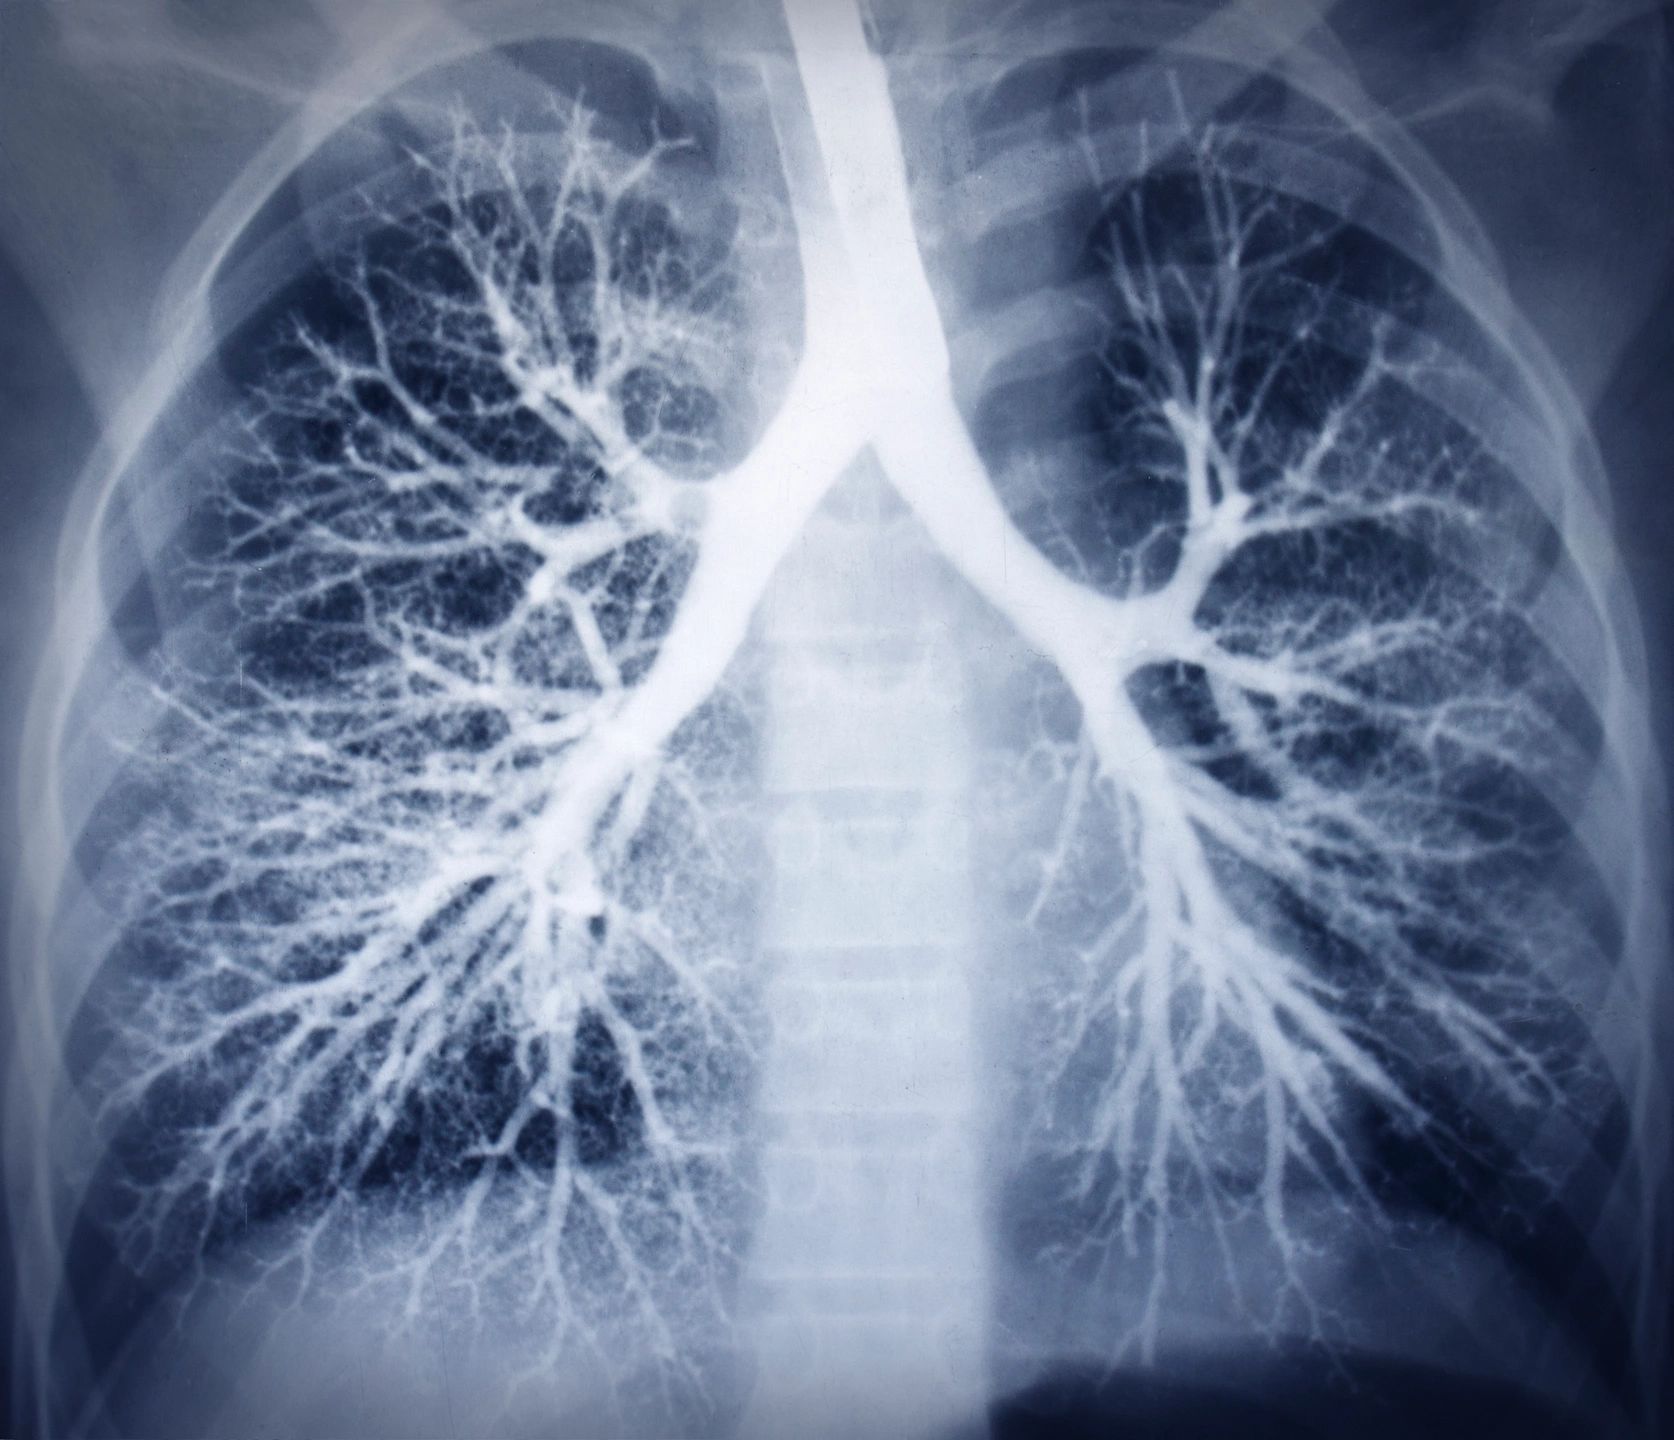

To start with, what exactly are the signs and symptoms of asthma? Common symptoms of asthma include shortness of breath, wheezing, coughing and/or wheezing attacks. You may also experience chest tightness or pain and even trouble sleeping due to difficulty breathing. Your asthma may be getting worse if you notice the symptoms are becoming more frequent and bothersome. For example, you may notice that your asthma is starting to interfere with your activities of daily living whereas in the past you did not notice such a large interruption in daily life. If your asthma is getting worse, you may also need to use a quick –relief inhaler more often. Lastly you may have an increase in difficulty breathing. These symptoms occur because when you have asthma your airways become narrow and swollen. You may also produce extra mucus. Please see the attached picture. (1)